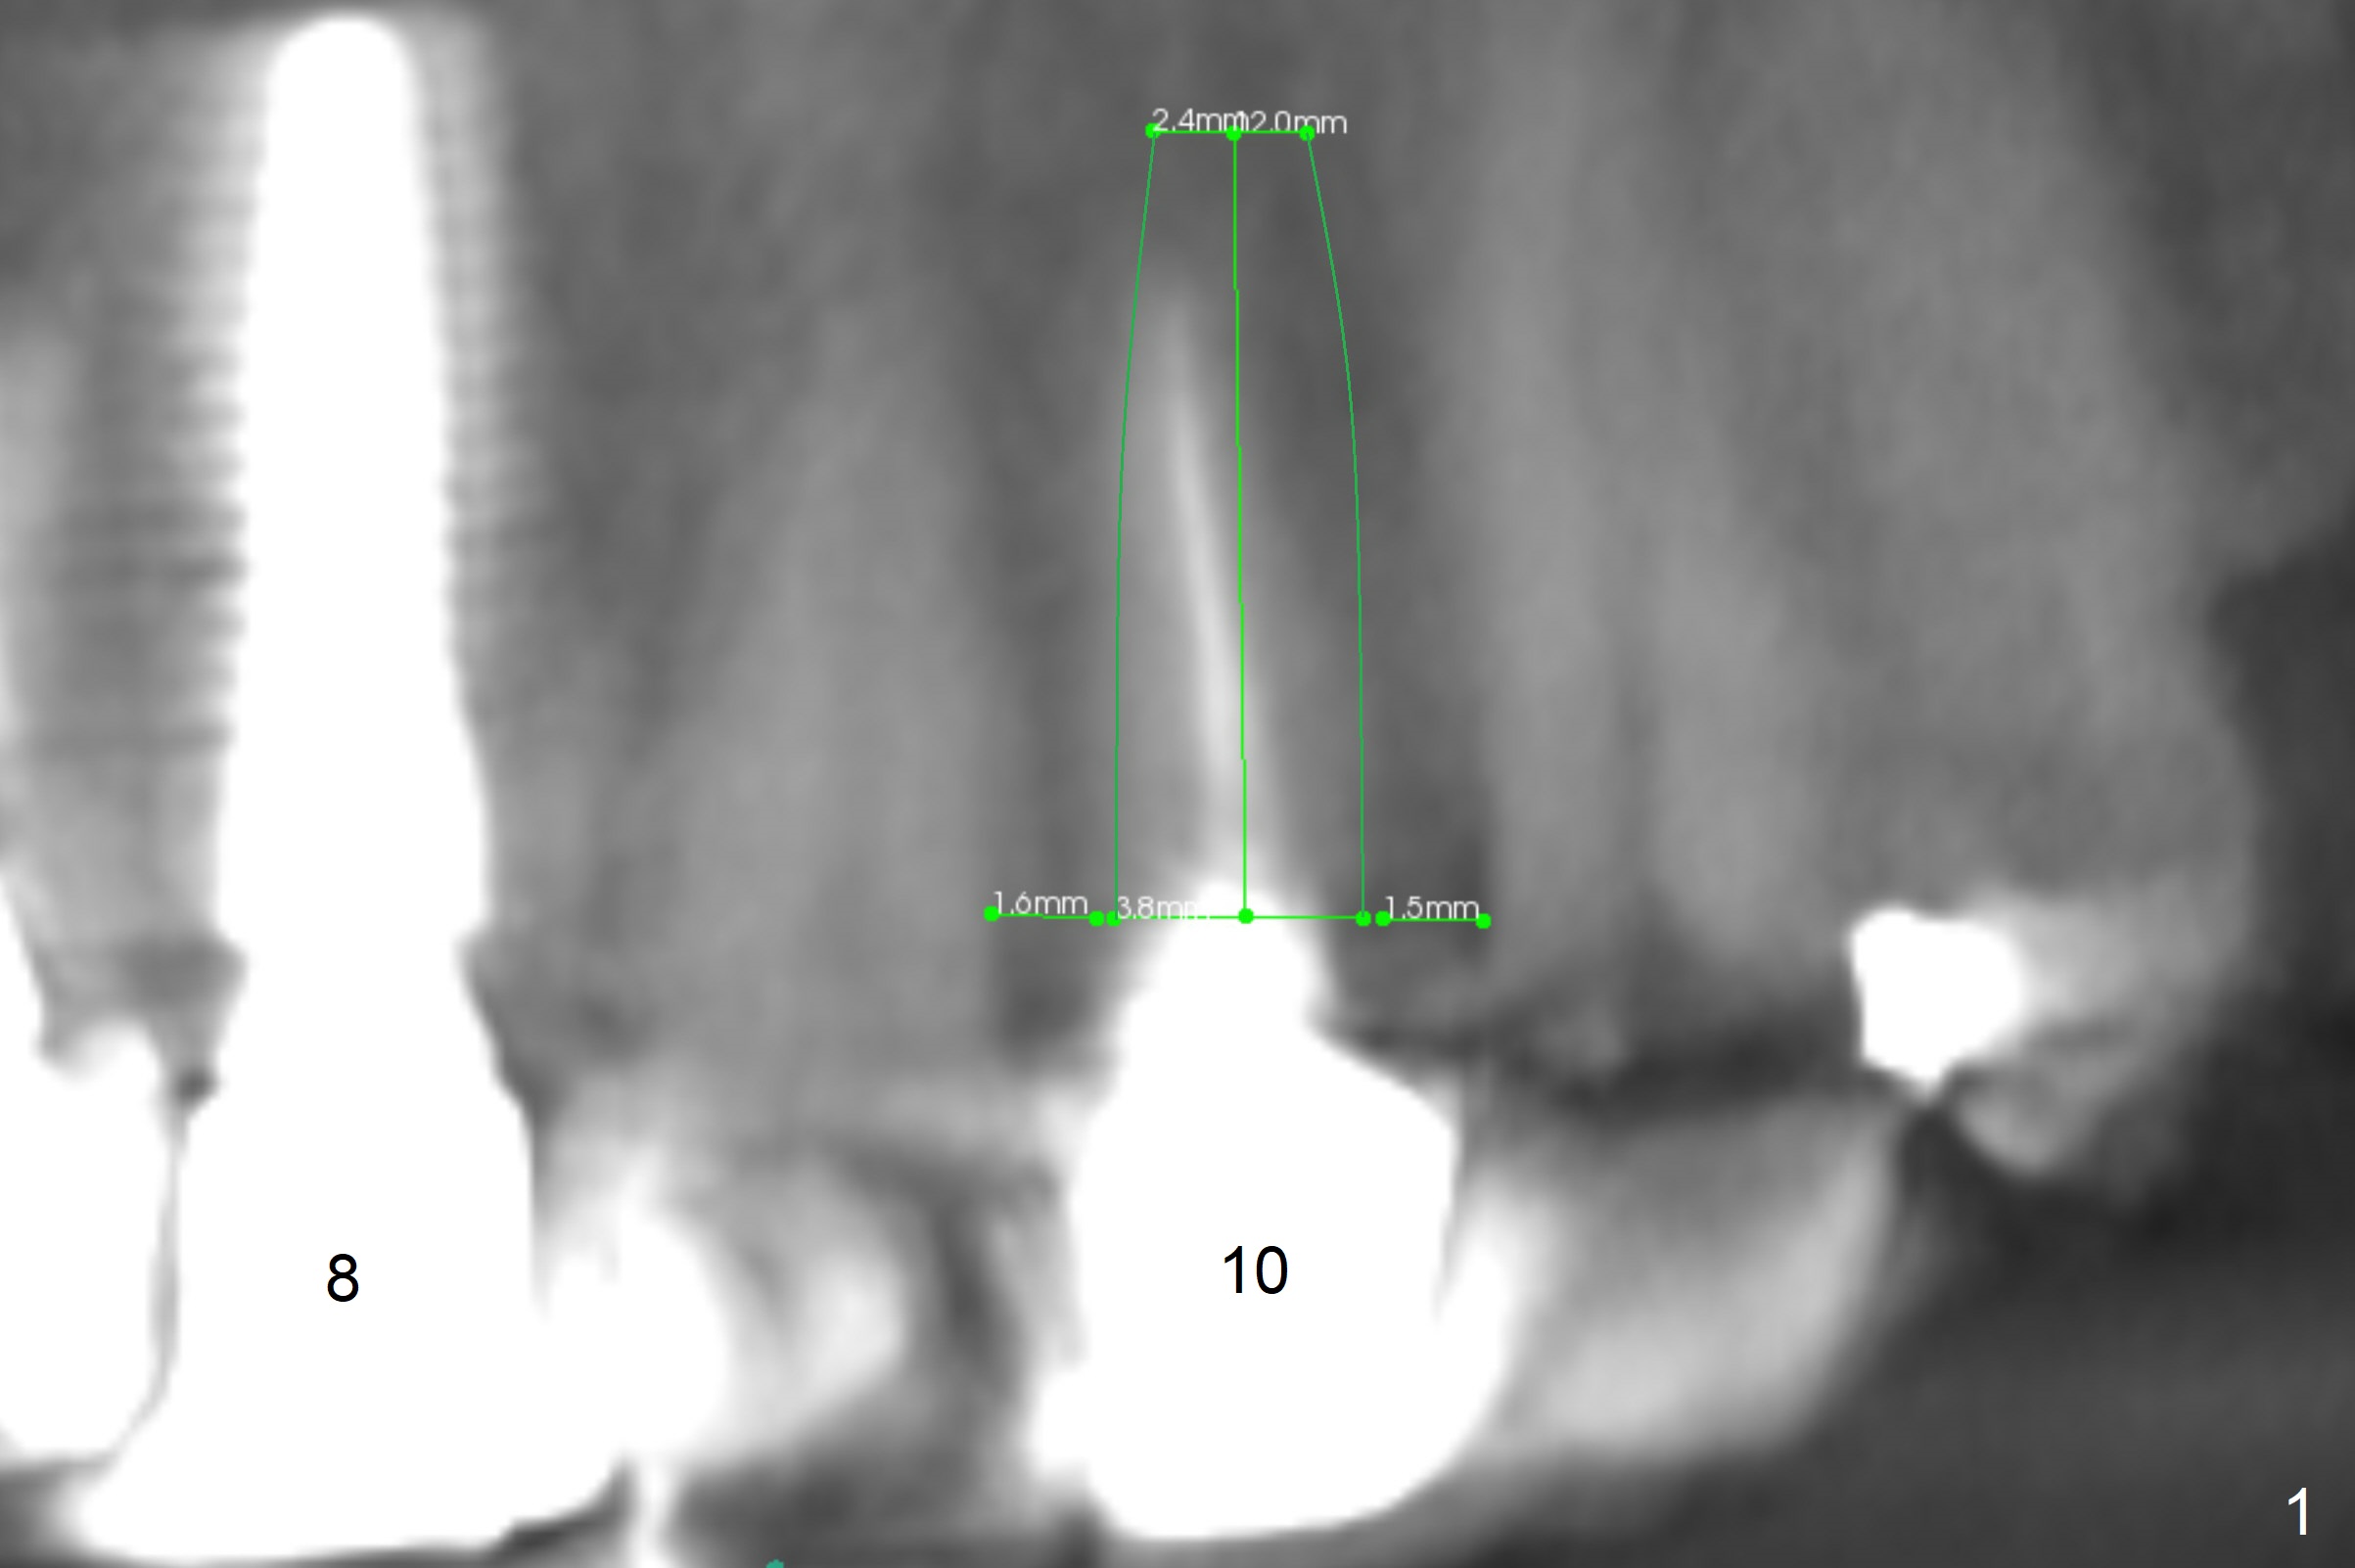

Narrow Mesiodistal Space

A 37-year-old woman needs an implant at #10 because of crown recementation twice (Fig.1). The smallest 2-piece implant, 3.8 mm, appears to be larger than the root. The implant may perforate the buccal apical concavity (Fig.2 arrowheads). Measure the extracted root. If it is wider than 3.8 mm mesiodistally, place the 2-piece implant. Otherwise use a 3 mm 1-piece one. Do not forget the angled one. Retrospectively, the 3.8 mm implant is large for the site. A 3.0 or 2.5 mm one is more appropriate (Fig.2).